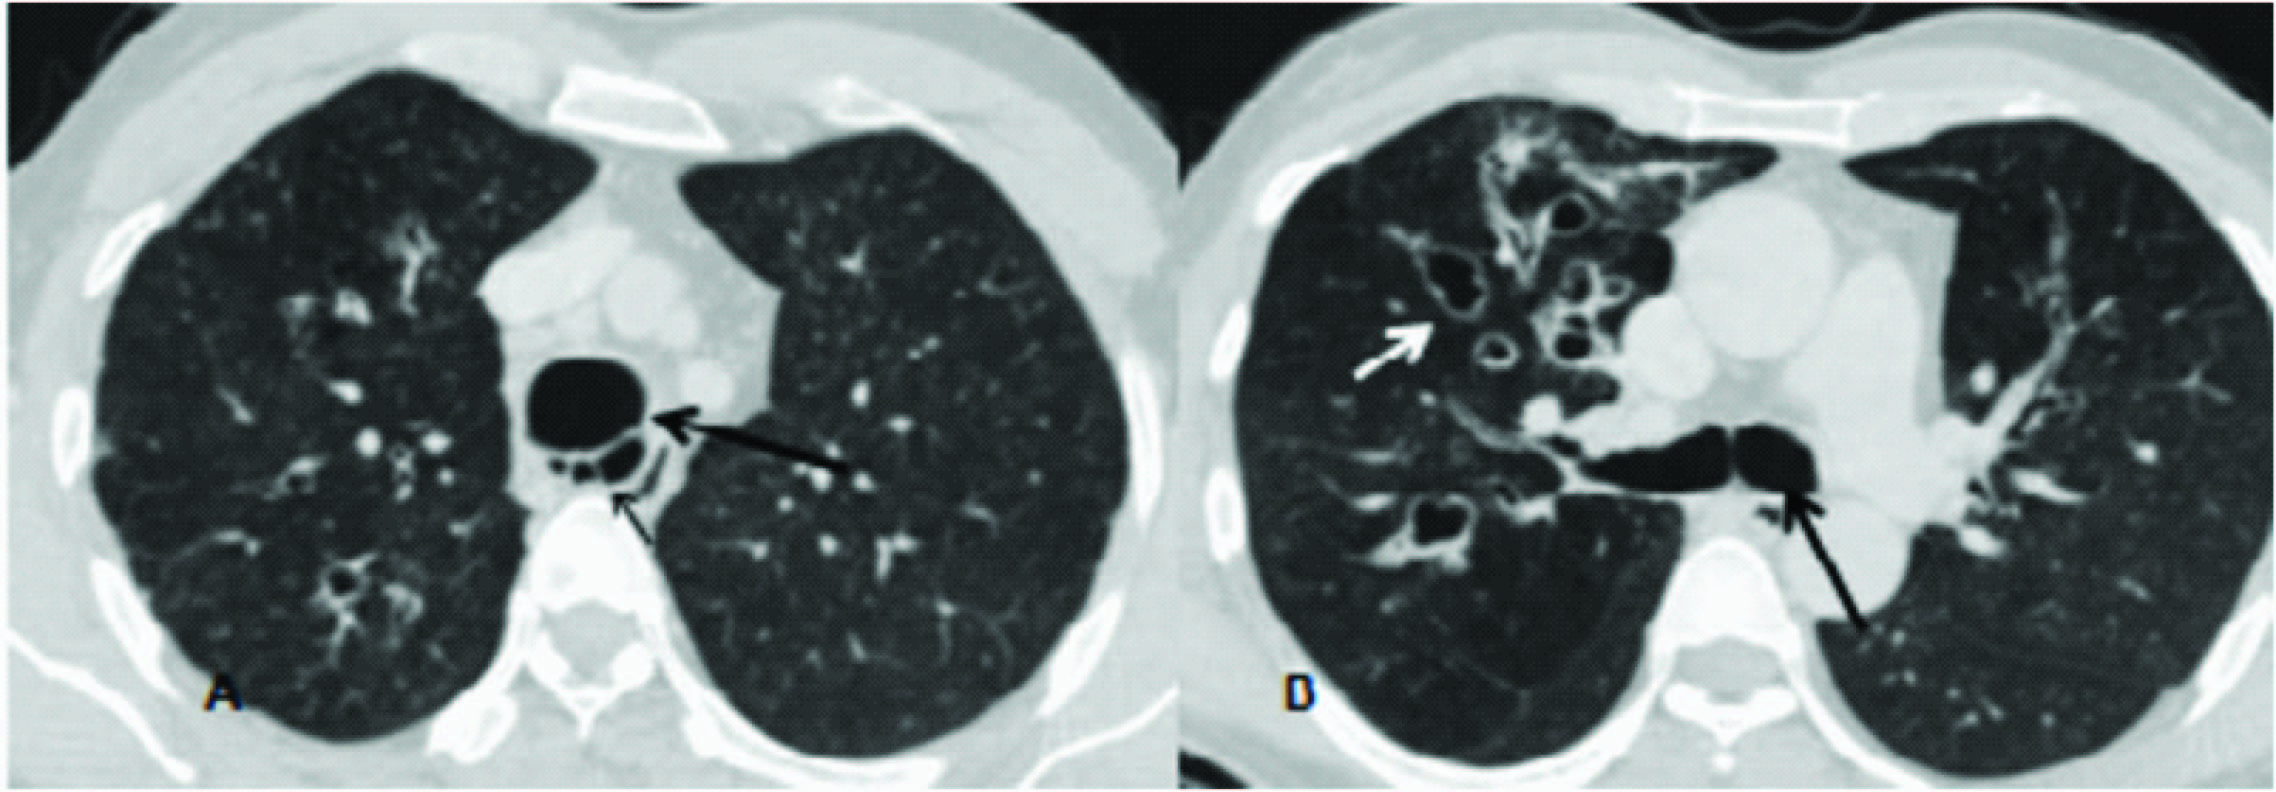

Axial CT chest sections –lung window (A,B) showing abnormal dilatation of tracheobronchial tree(large arrows) with small arrow in A showing tracheal wall diverticulae and small arrow in B showing cystic bronchiectasis,

Computed tomography revealed abnormally dilated trachea and bilateral main stem bronchus.The transverse diameter of trachea (2 cm proximal to arch of aorta) was 30 mm, with diameter of right and left main bronchus being 19.5 mm and 18.5mm respectively. There were associated multiple diverticulae/sacculations seen arising from intrathoracic trachea and proximal main stem bronchus with bilateral cystic broncheictasis [Table/Fig-1,2,3] and mosaic attenuation in bilateral lung fields. The post processed thick minimal intensity images (MinIP [Table/Fig-2] were particularly useful in demonstrating dilated tracheobronchial tree and also mosaic attenuation in bilateral lung fields which can either be due to associated small airway disease or pulmonary artery hypertension. Thus based on imaging findings the diagnosis of Mounier-Kuhn syndrome was given. Fibero-optic bronchoscopy further confirmed the diagnosis of abnormally dilated tracheobronchial tree and patient was started on chest physiotherapy and oral antibiotics.